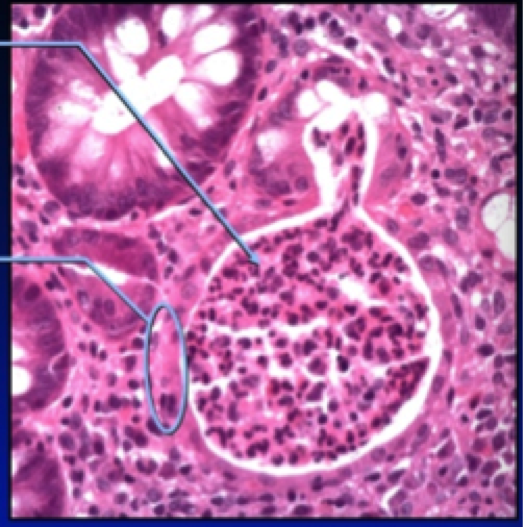

What is this? What does the arrow point to? the circle?

Crypt abscess. Feature of Ulcerative Colitis

Arrow: neutrophils accumulated in and expanding the gland lumen.

Circle: injured epithelial cells, eosinophilic cytoplasm, loss of mucin, apoptosis.